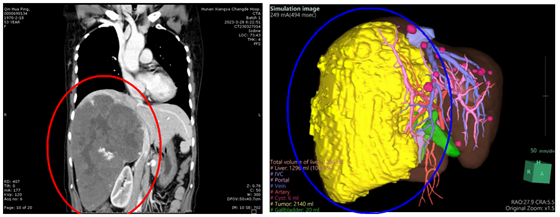

患者CT影像图及3D重建图提示“肝占位性病变”

当地医生建议她转往上级医院做进一步治疗,如果不及时治疗,一旦受到意外压力,快速生长的血管瘤可能破裂危及生命。秦女士抱着希望来到湘雅常德医院肝胆外科的时候,肖广发主任面对检查结果也非常吃惊,片子上展现出的是一个巨大的肝脏血管瘤。瘤子占据了右侧腹腔的大部分,已将右侧腰背侧的肾脏推挤至肚脐右侧,经过测量,血管瘤直径近25厘米,重达5斤!

肖广发主任带领肝胆胰外科团队组织科室内讨论,运用3D虚拟技术精准判断各血管关系及剩余肝体积的大小,为患者制定了周密的手术计划,对术中各种突发情况做好预案,同时与患者及其家属就患者病情、各项治疗方案及其利弊、手术风险等进行详细的沟通。